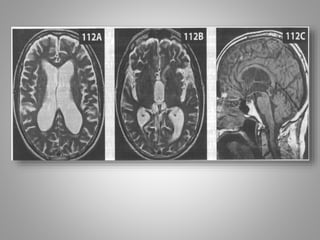

Обстурктивна некомунікативна

гідроцефалія.

• Дитина із скаргами на головний біль вранці.

• Отримані зображення

• Помітне розширення III і бічних шлуночків на Т2-

зважених зображеннях (110 А, В). На сагітальному

знімку в режимі Т1 (110С) видно розтягнутий III

щлуночок і нормальний за розміром IV шлуночок.

• Крім того, є очевидний стеноз або оклюзія сільвієвого

водопроводу.

• Крім того, є очевидний стеноз або оклюзія

сільвієвого водопроводу.